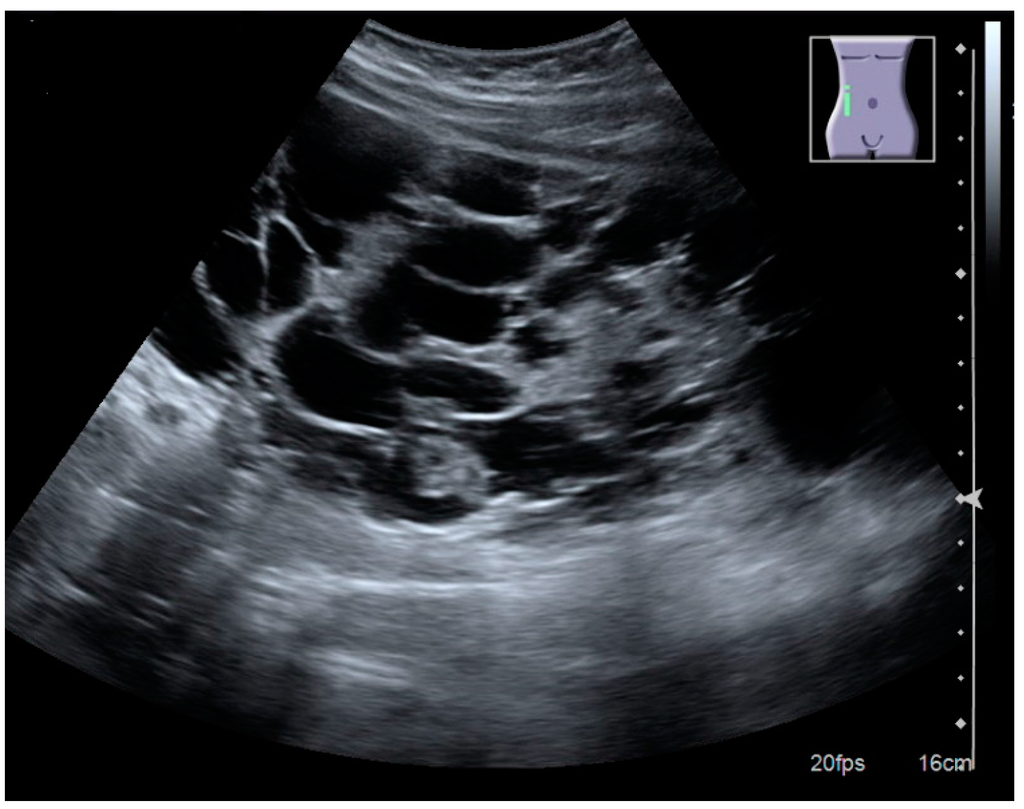

In polycystic kidney disease, multiple cysts of varying size in close contact with each other are seen filling virtually the entire renal region. In advanced stages of this disease, the kidneys are enlarged with a lack of corticomedullary differentiation (Figure 7) [17].

Figure 7. Advanced polycystic kidney disease with multiple cysts.